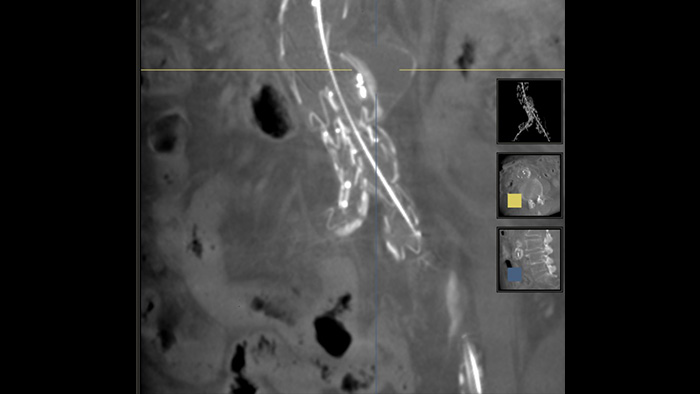

SmartCT Soft Tissue

SmartCT Soft Tissue - Visualización similar a una TC de los vasos

SmartCT Soft Tissue es una técnica de adquisición de rayos X que genera una visualización similar a una TC de tejido blando en relación con otras estructuras durante los procedimientos, todo controlado a través de la pantalla táctil en la mesa. Puede utilizar las imágenes similares a la TC para evaluar el tejido blando, la estructura ósea y la implementación del stent antes, durante y después de los procedimientos de intervención. Esta técnica es particularmente útil para comprobar si hay complicaciones después de procedimientos (complejos) de reparación endovascular de aneurismas (REVA).